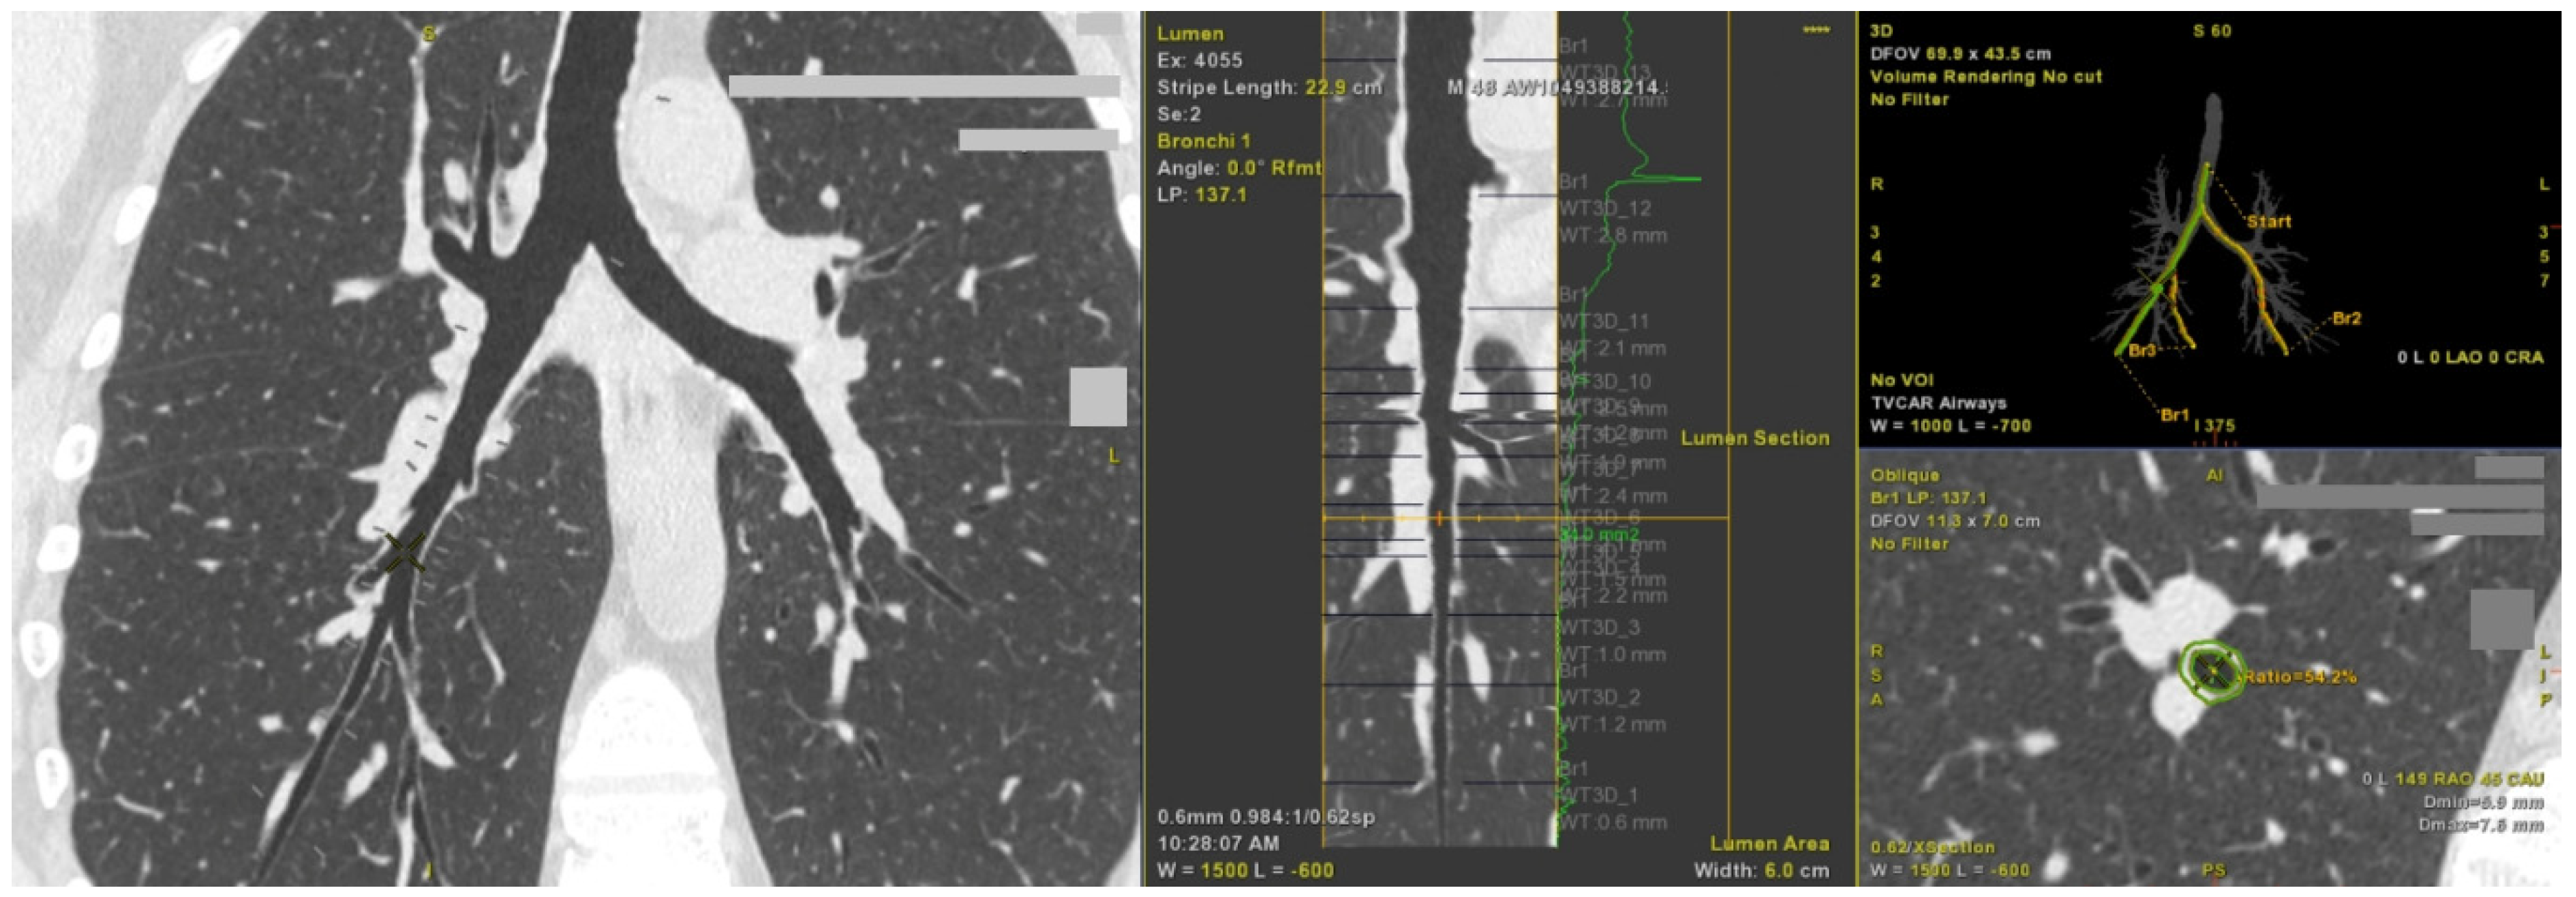

2.2. Computed Tomography Imaging Shows Airway Wall Thickening in Asthma Patients with Persistent Airflow Limitation

4.2. Lung CT

- Kozlik, P.; Zuk, J.; Bartyzel, S.; Zarychta, J.; Okon, K.; Zareba, L.; Bazan, J.G.; Kosalka, J.; Soja, J.; Musial, J.; et al. The Relationship of Airway Structural Changes to Blood and Bronchoalveolar Lavage Biomarkers, and Lung Function Abnormalities in Asthma. Clin. Exp. Allergy 2020, 50, 15–28. [Google Scholar] [CrossRef] [PubMed]